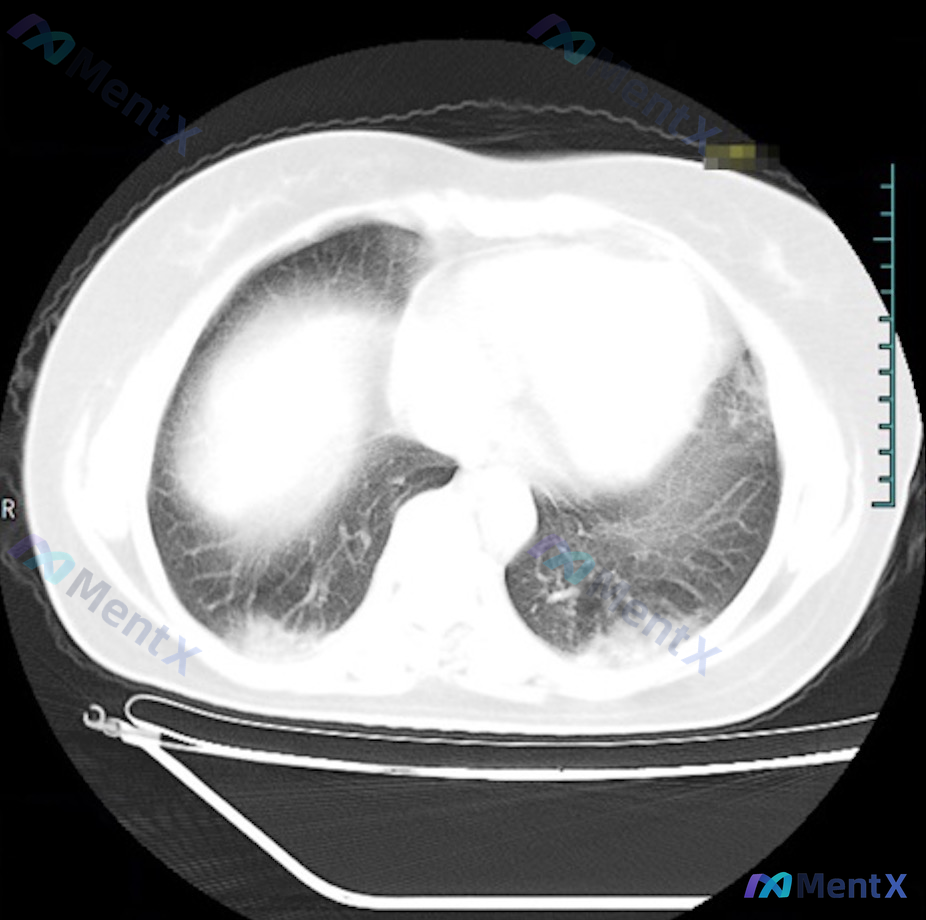

这个双肺底对称性实变磨玻璃影,第一反应会先考虑感染吗?

整理到一份胸部CT肺窗横断面的影像分析资料,先不放临床背景,只看影像特征,大家第一眼的鉴别思路会怎么排?

核心影像表现:

- 病灶位置:严格局限于双肺下叶背侧近后胸壁处(坠积部位),双侧对称

- 密度:以实性为主,伴部分磨玻璃样改变

- 边缘:模糊,与正常肺组织界限不清

- 其他:未见明确结节、空洞或肿块;支气管开口基本通畅;未见明显胸腔积液

这个“背侧坠积分布”的特点,会不会改变你第一眼先考虑“感染性肺炎”的惯性?